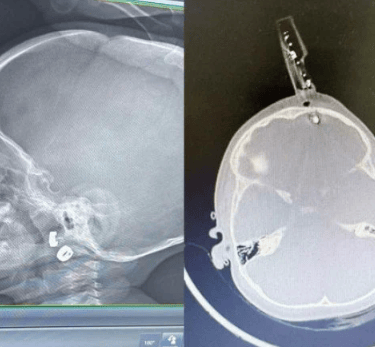

Carregador fica preso no crânio de bebê - (crédito: Cedido ao Correio)

Um acidente doméstico grave envolvendo uma criança de 1 ano e 4 meses mobilizou equipes médicas em Divinópolis, no Centro-Oeste de Minas Gerais. O bebê caiu da cama dentro de casa e acabou tendo um carregador de celular cravado na região frontal do crânio, com perfuração até o cérebro. Apesar da gravidade, a criança passou por cirurgia de emergência e apresentou evolução clínica positiva, recebendo alta hospitalar após alguns dias de internação.

Segundo informações médicas, a criança estava sobre a cama quando caiu no chão do quarto. Próximo ao local havia um carregador comum de celular. Durante a queda, um dos pinos metálicos do carregador atravessou a testa do bebê, atingindo a região frontal do crânio, próxima aos olhos.

Exames de imagem confirmaram que o pino metálico transfixou o osso do crânio, que em crianças dessa idade ainda é extremamente fino, e atingiu o lobo frontal do cérebro.